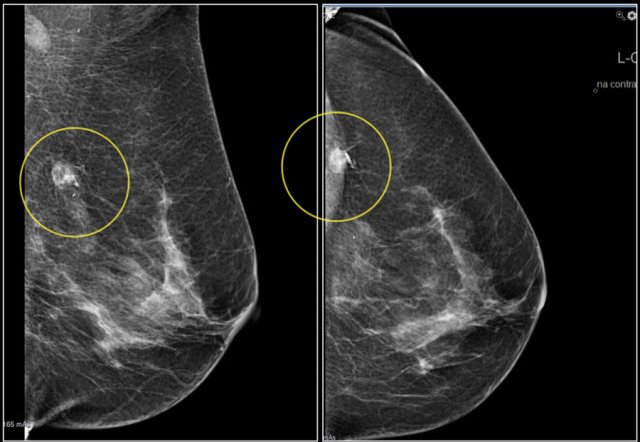

Notice the distortion of the normal breast architecture on oblique view (yellow circle) and magnification view.

A resection was performed and only scar tissue was found in the specimen.